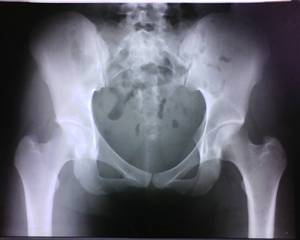

Рентгенография 02.07.12 (лежа, носки вместе, пятки врозь) http://s003.radikal.ru/i202/1207/b1/1e6a13b7bf78.jpg

тута стадия 3 наличи ренгтен прозрачной линии (признак полумесяца ) ,положение А-медиальное. на кт необходимо определить распространенность уплощения головки в милиметрах(классификация ARCO) .для стадирования на более ранних стадиях необходимо было сделать радионуклидное исследование.а так диагноз поставлен точно

3-я стадия АНГБК? Собственно сейчас болей в паху нет (около недели), есть периодическая слабая боль в области большого вертела и по передней пов-ти н/3 бедра, плюс парестезии в голени и стопе. Неврологи подозревают грыжу диска L5-S1. Уважаемые рентгенологи, может кто-то еще высказать мнение? Спасибо.